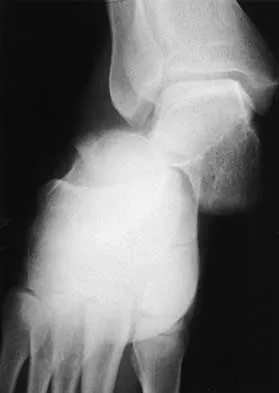

A 47-year-old man has an acute swollen, red, painful first metatarsophalangeal joint. He denies any history of similar symptoms. What is the first step in evaluation?

Explanation

The patient's symptoms are typical for gouty arthropathy, and the diagnosis can only be confirmed with aspiration and visualization of the crystals. A concomitant infection also must be ruled out; therefore, it is important to obtain a cell count and culture. Colchicine may have a role in gouty management, but the diagnosis must be confirmed. Allopurinol is not effective in acute gouty arthropathy. Measurement of serum uric acid levels is often not helpful in making a definitive diagnosis. Steroid injections should be deferred until cell count and culture results indicate no accompanying infection. Richardson EG (ed): Orthopaedic Knowledge Update: Foot and Ankle 3. Rosemont, IL, American Academy of Orthopaedic Surgeons, 2004, pp 172-173.